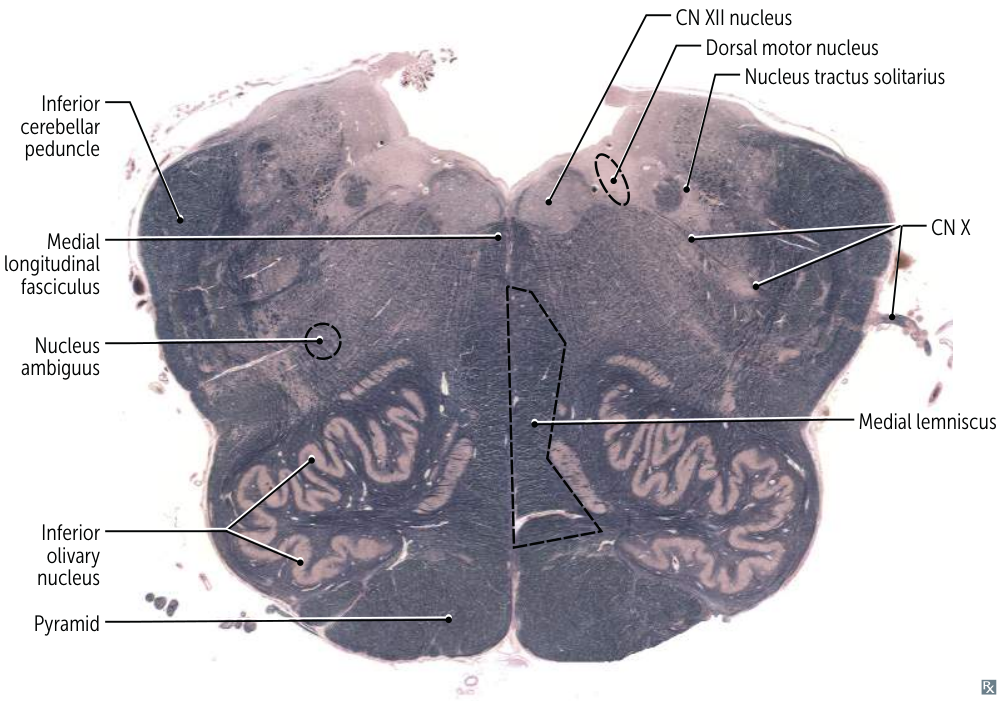

- Rostral Medulla (Open Medulla):

- Most Distinctive Feature: The large, highly convoluted (“squiggly”) Inferior Olivary Nucleus. The fourth ventricle is open (“open medulla”).

- CN VIII (Vestibulocochlear) nuclei (partly): The Vestibular nuclei extend significantly into the medulla.

- CN IX (Glossopharyngeal) nuclei: Involved in taste from the posterior third of the tongue, sensation from the pharynx, salivation (parotid gland), and swallowing. Key nuclei include parts of the Nucleus Ambiguus, Solitary Nucleus, and Inferior Salivatory Nucleus.

- CN X (Vagus) nuclei: Involved in swallowing, speech, parasympathetic control of the heart, lungs, and abdominal organs, sensation from the pharynx and larynx, and taste from the epiglottis. Key nuclei include the Dorsal Motor Nucleus of the Vagus, Nucleus Ambiguus, and Solitary Nucleus.

- CN XI (Accessory) nucleus (Cranial Part): The cranial root originates from the Nucleus Ambiguus and joins the vagus nerve to innervate laryngeal muscles. (The main spinal part arises from the cervical spinal cord).

- CN XII (Hypoglossal) nucleus: Controls tongue movements.

- (Also contains the lower part of the Spinal Trigeminal Nucleus (CN V) processing facial pain and temperature).